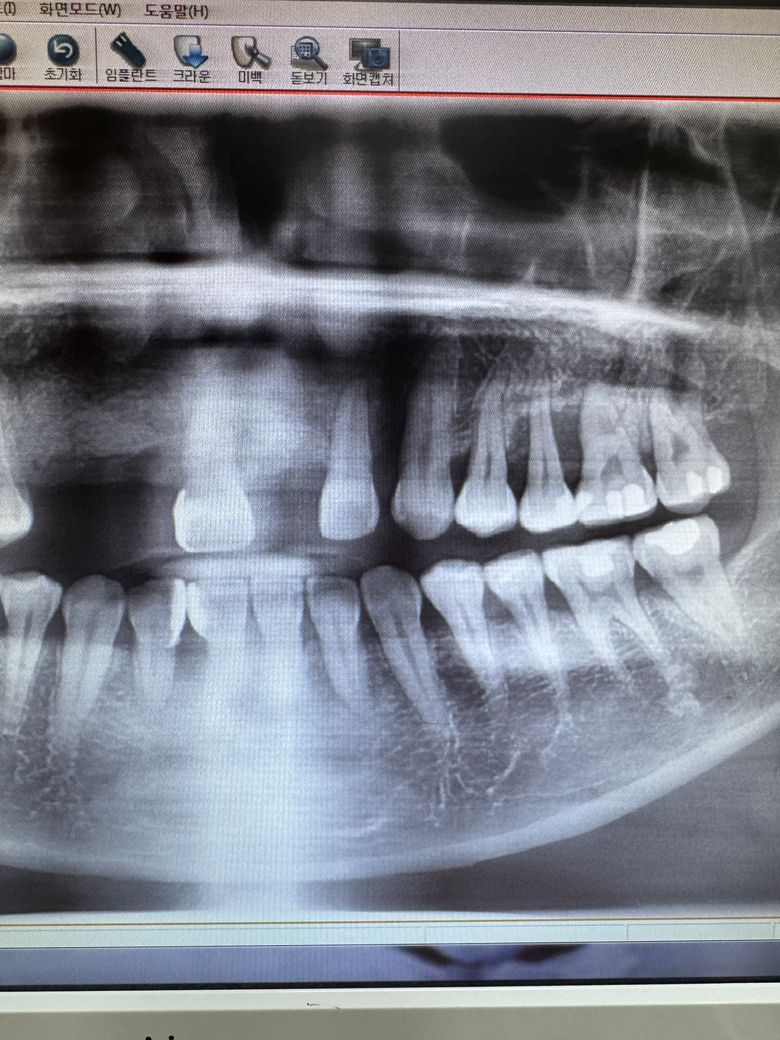

잇몸이 부어서 앞니 발치했는데 어금니도 발치해야할까요?

안녕하세요 저는 36살 여자입니다 잇몸이 붓고 가라앉고를 반복하다 앞니3개를 발치하고 뼈이식후 임플란트 대기중이에요 현재 지금 어금니쪽 잇몸이 부어서 상당히 아파요 ㅠㅠ 제가 췌장이식 받은지 10년차인데 면역억제제 복욕중이고 혈액투석중에 있어요 제가 궁금한것은 제 치아를 살려서 쓰고싶은데 선생님들의 견해마다 달라서 발치를 해야할까요? 최소 3개 라고 보시는거 같은데 부모님이 주신 하나밖에 없는 저의 영구치를 잃어야 한다는게 너무 속상해요

• 2번 째 사진

사진상에 오른쪽위 치아도 잇몸뼈가 많이 안좋은거 같습니다. 발치를 하시는게 좋을것같습니다.